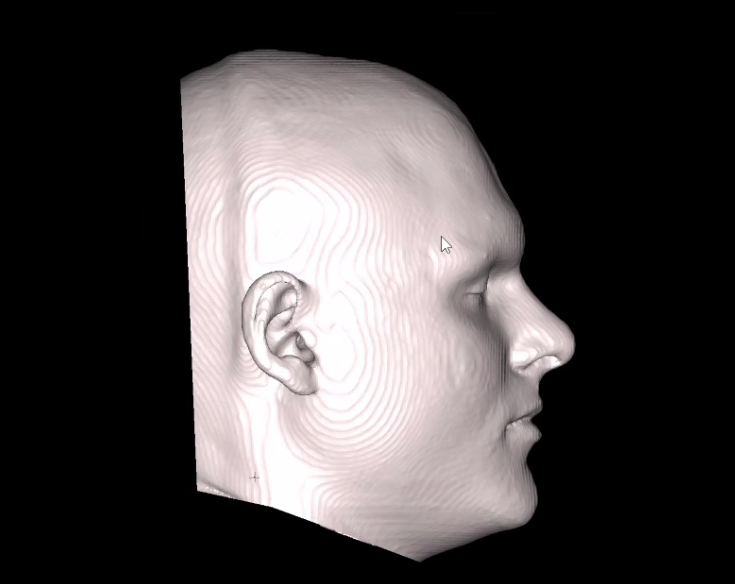

Here are my current CT Scans:

Here are the predicted CT Scans with the Genioplasty:

Here are my current CT Scans:

Here are the predicted CT Scans with the Genioplasty: